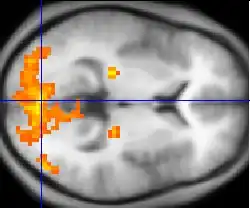

Neuroimaging

Neuroimaging has contributed to the identification of the neural components involved in drug reinstatement as well as drug-taking determinants such as the pharmokinetics, neurochemistry, and dose of the drug. The neuroimaging techniques used in non-human primates include positron emission tomography (PET), which uses radiolabeled ligand tracers to measure neurochemistry in vivo and single-photon emission computed tomography (SPECT).[3] Functional magnetic resonance imaging (fMRI) is widely used in human subjects because it has much higher resolution and eliminates exposure to radiation.[14]